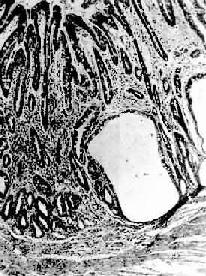

图10-3 慢性萎缩性胃炎 幽门腺大部分萎缩消失,胃小凹延长,有潴留性小囊形成,腺上皮中杂有不少杯状细胞(肠上皮化生),固有膜内有不少慢性炎性细胞浸润(Ⅱ74-4950) 胃粘膜的肠上皮化生分为小肠型及大肠型二种,二型中又分别分出完全肠上皮化生与不全肠上皮化生(图10-4)。小肠型与大肠型肠上皮化生可从光镜的腺体形态及粘液组化反应加以鉴别。Teglbjaerg曾报告含氧乙酰化唾液酸粘液者为大肠型化生,该粘液反应阴性者为小肠型化生。多数研究指出大肠型化生与肠型胃癌并存者较多,特别是不全大肠型肠上皮化生在癌旁组织中明显增多,其DNA含量及CEA的检出率均明显增加。但肠上皮化生究竟是否属于癌前病变迄今尚无定论。